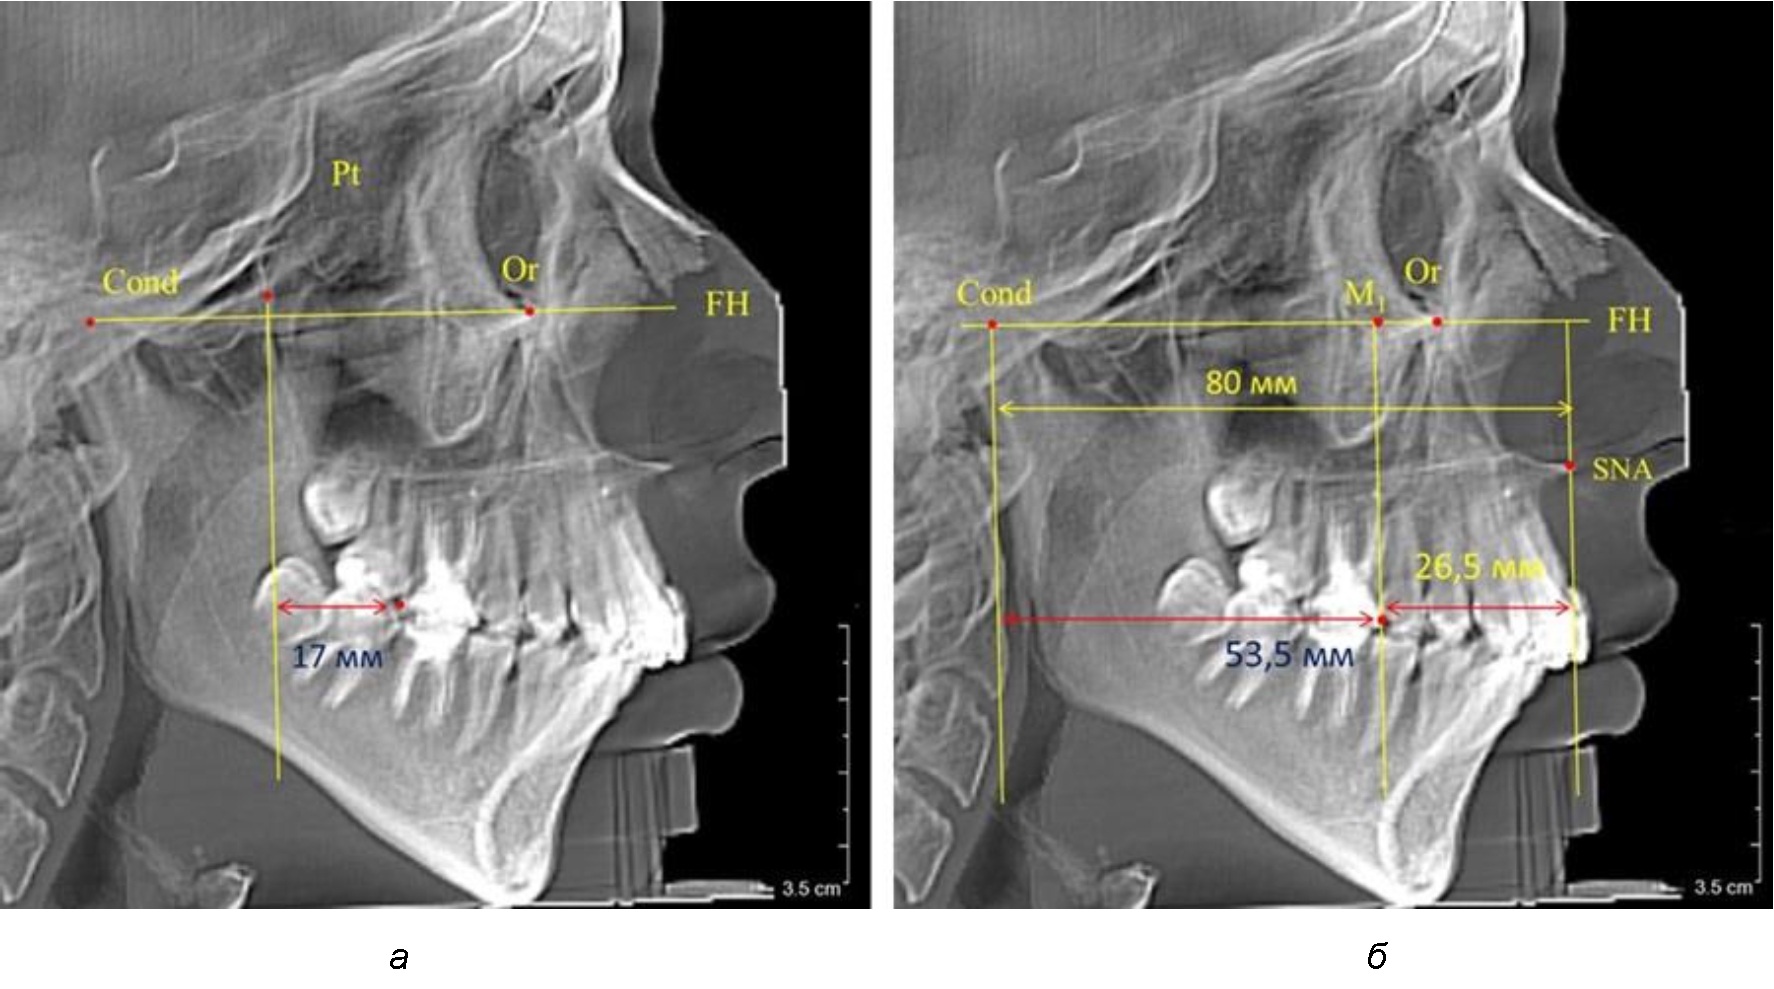

Рис. 2. Особенности положения первых моляров по R. E. McDonald (а) и по предложенному методу (б) при уменьшенном молярно-крыловидном расстоянии

Рис. 3. Особенности положения первых моляров по R. E. McDonald (а) и по предложенному методу (б) при увеличенном молярно-крыловидном расстоянии

Так, при расстоянии от крыловидной вертикальной плоскости PTV до дистальной поверхности верхнего первого постоянного моляра в 13 мм сагиттальный размер гнатического отдела был 82 мм. При этом отношение кондилярно-спинального расстояния к кондилярно-молярному размеру (54,5) было близким к коэффициенту 1,5, что представлено на рис. 2.

В то же время при увеличенном расстоянии от крыловидной вертикальной плоскости PTV до дистальной поверхности верхнего первого постоянного моляра, равное 23 мм, сагиттальный размер гнатического отдела составил 92 мм. При этом отношение кондилярно-спинального расстояния к кондилярно-молярному размеру (30,5), так же, как и при малых размерах, было близким к коэффициенту 1,5, что представлено на рис. 3.

Таким образом, наблюдалась эффективность использования относительных показателей при определении положения первых постоянных моляров. При этом наиболее целесообразно и с методологической точки зрения верным, было использование медиальной поверхности первого постоянного моляра. Построенная таким образом молярная линия отграничивала отдел зубной дуги с замещающими зубами от дистального отдела с добавочными зубами постоянного прикуса, в частности, постоянных моляров.

Второй частью исследования был анализ положения первых постоянных моляров в различные периоды сменного прикуса. На телерентгенограммах детей периода прикуса молочных зубов дистальная поверхность зачатка первого постоянного моляра отстояла от крыловидной вертикали на величину, составляющую около 7 мм, что было близким по значению к данным R. E. McDonald. Сагиттальный размер гантического отдела составлял около 60 мм, а его отношение к кондилярно-молярной глубине – 1,5 (рис. 4).

По мере роста челюстей увеличивалась глубина гнатического отдела лица, и кондиллярно-спинальный размер составлял в среднем (74,57 ± 0,93) мм. Дистальная поверхность первого постоянного моляра отстояла от крыловидной вертикали на величину, составляющую около 11 мм, что, так же, как и в периоде прикуса молочных зубов, было близким по значению к данным R. E. McDonald, а именно возраст, плюс 3 мм. Однако величина ошибки среднего значения свидетельствовала о вариабельности признака даже в восьмилетнем возрасте после замены передней группы зубов и установки ключевых постоянных моляров в окклюзионное равновесие. Обращает на себя внимание отношение глубины гнатического отдела лица к дистальному отделу, а именно к кондилярно-молярному расстоянию (рис. 5).

Рис. 4. Особенности положения первых моляров по R. E. McDonald (а) и по предложенному методу (б) у ребенка 4 лет

Рис. 5. Особенности положения первых моляров по R. E. McDonald (а) и по предложенному методу (б) у ребенка 8 лет

После прорезывания вторых постоянных моляров кондилярно-спинальный увеличивался до 80 мм.

Дистальная поверхность первого постоянного моляра отстояла от крыловидной вертикали на величину, составляющую около 18 мм, что, так же, как и в предыдущих периодах прикуса, было близким по значению к данным R. E. McDonald, а именно возраст, плюс 3 мм.

Обращает на себя внимание отношение глубины гнатического отдела лица к дистальному отделу, а именно к кондилярно-молярному расстоянию, которое, вне зависимости от сагиттальных размеров, составляло 1 : 1,5.

Рентгенограмма 16-летнего ребенка, с реперными линиями и анализируемыми линейными параметрами по двум используемым методам, представлена на рис. 6.

Рис. 6. Особенности положения первых моляров по R. E. McDonald (а) и по предложенному методу (б) у ребенка 16 лет